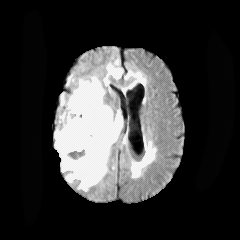

We introduce a neural network framework, utilizing adversarial learning to partition an image into two cuts, with one cut falling into a reference distribution provided by the user. This concept tackles the task of unsupervised anomaly segmentation, which has attracted increasing attention in recent years due to their broad applications in tasks with unlabelled data. This Adversarial-based Selective Cutting network (ASC-Net) bridges the two domains of cluster-based deep learning methods and adversarial-based anomaly/novelty detection algorithms. We evaluate this unsupervised learning model on BraTS brain tumor segmentation, LiTS liver lesion segmentation, and MS-SEG2015 segmentation tasks. Compared to existing methods like the AnoGAN family, our model demonstrates tremendous performance gains in unsupervised anomaly segmentation tasks. Although there is still room to further improve performance compared to supervised learning algorithms, the promising experimental results shed light on building an unsupervised learning algorithm using user-defined knowledge.